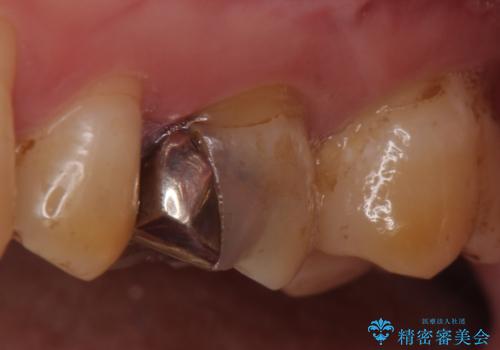

- 他院にて左上6番目の歯の神経が死んでいるといわれたので診て欲しいといらっしゃった方の症例です。

診査の結果左上6は失活していたため、根管治療を行った後にオールセラミッククラウンによる補綴を行いました。